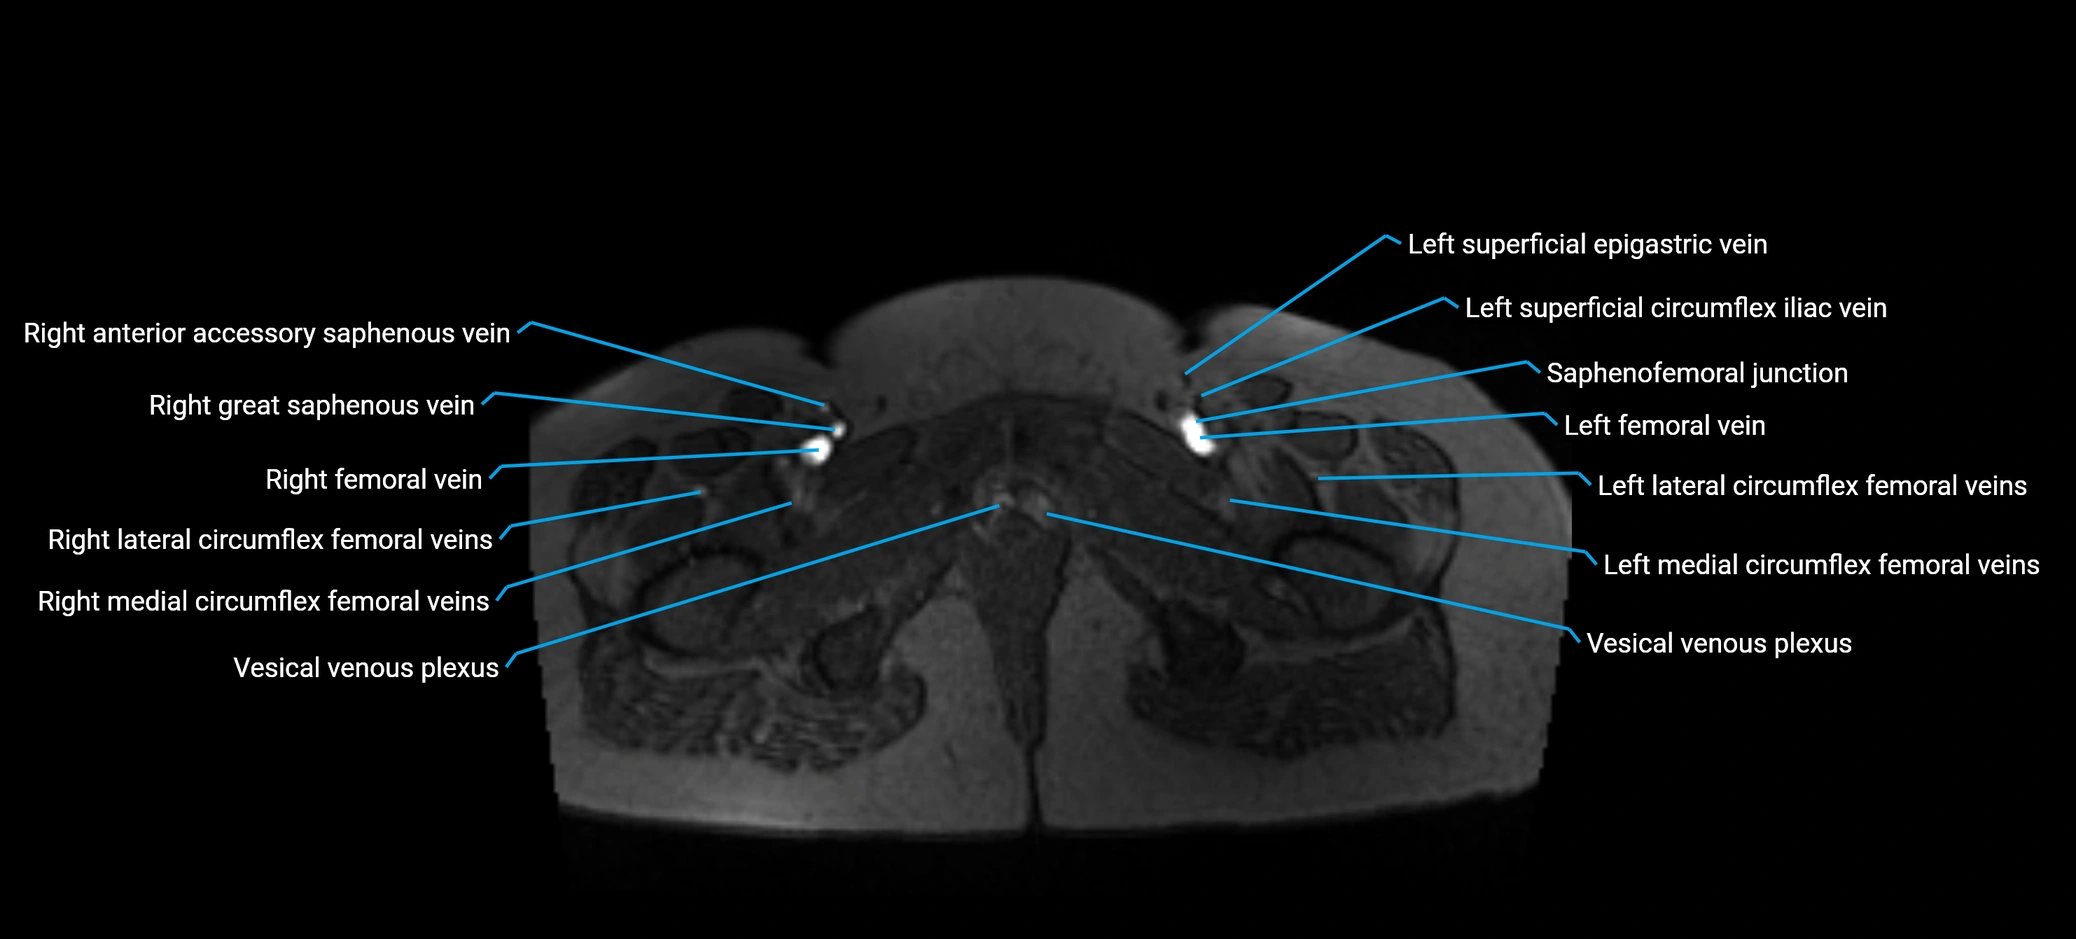

MRI image

image